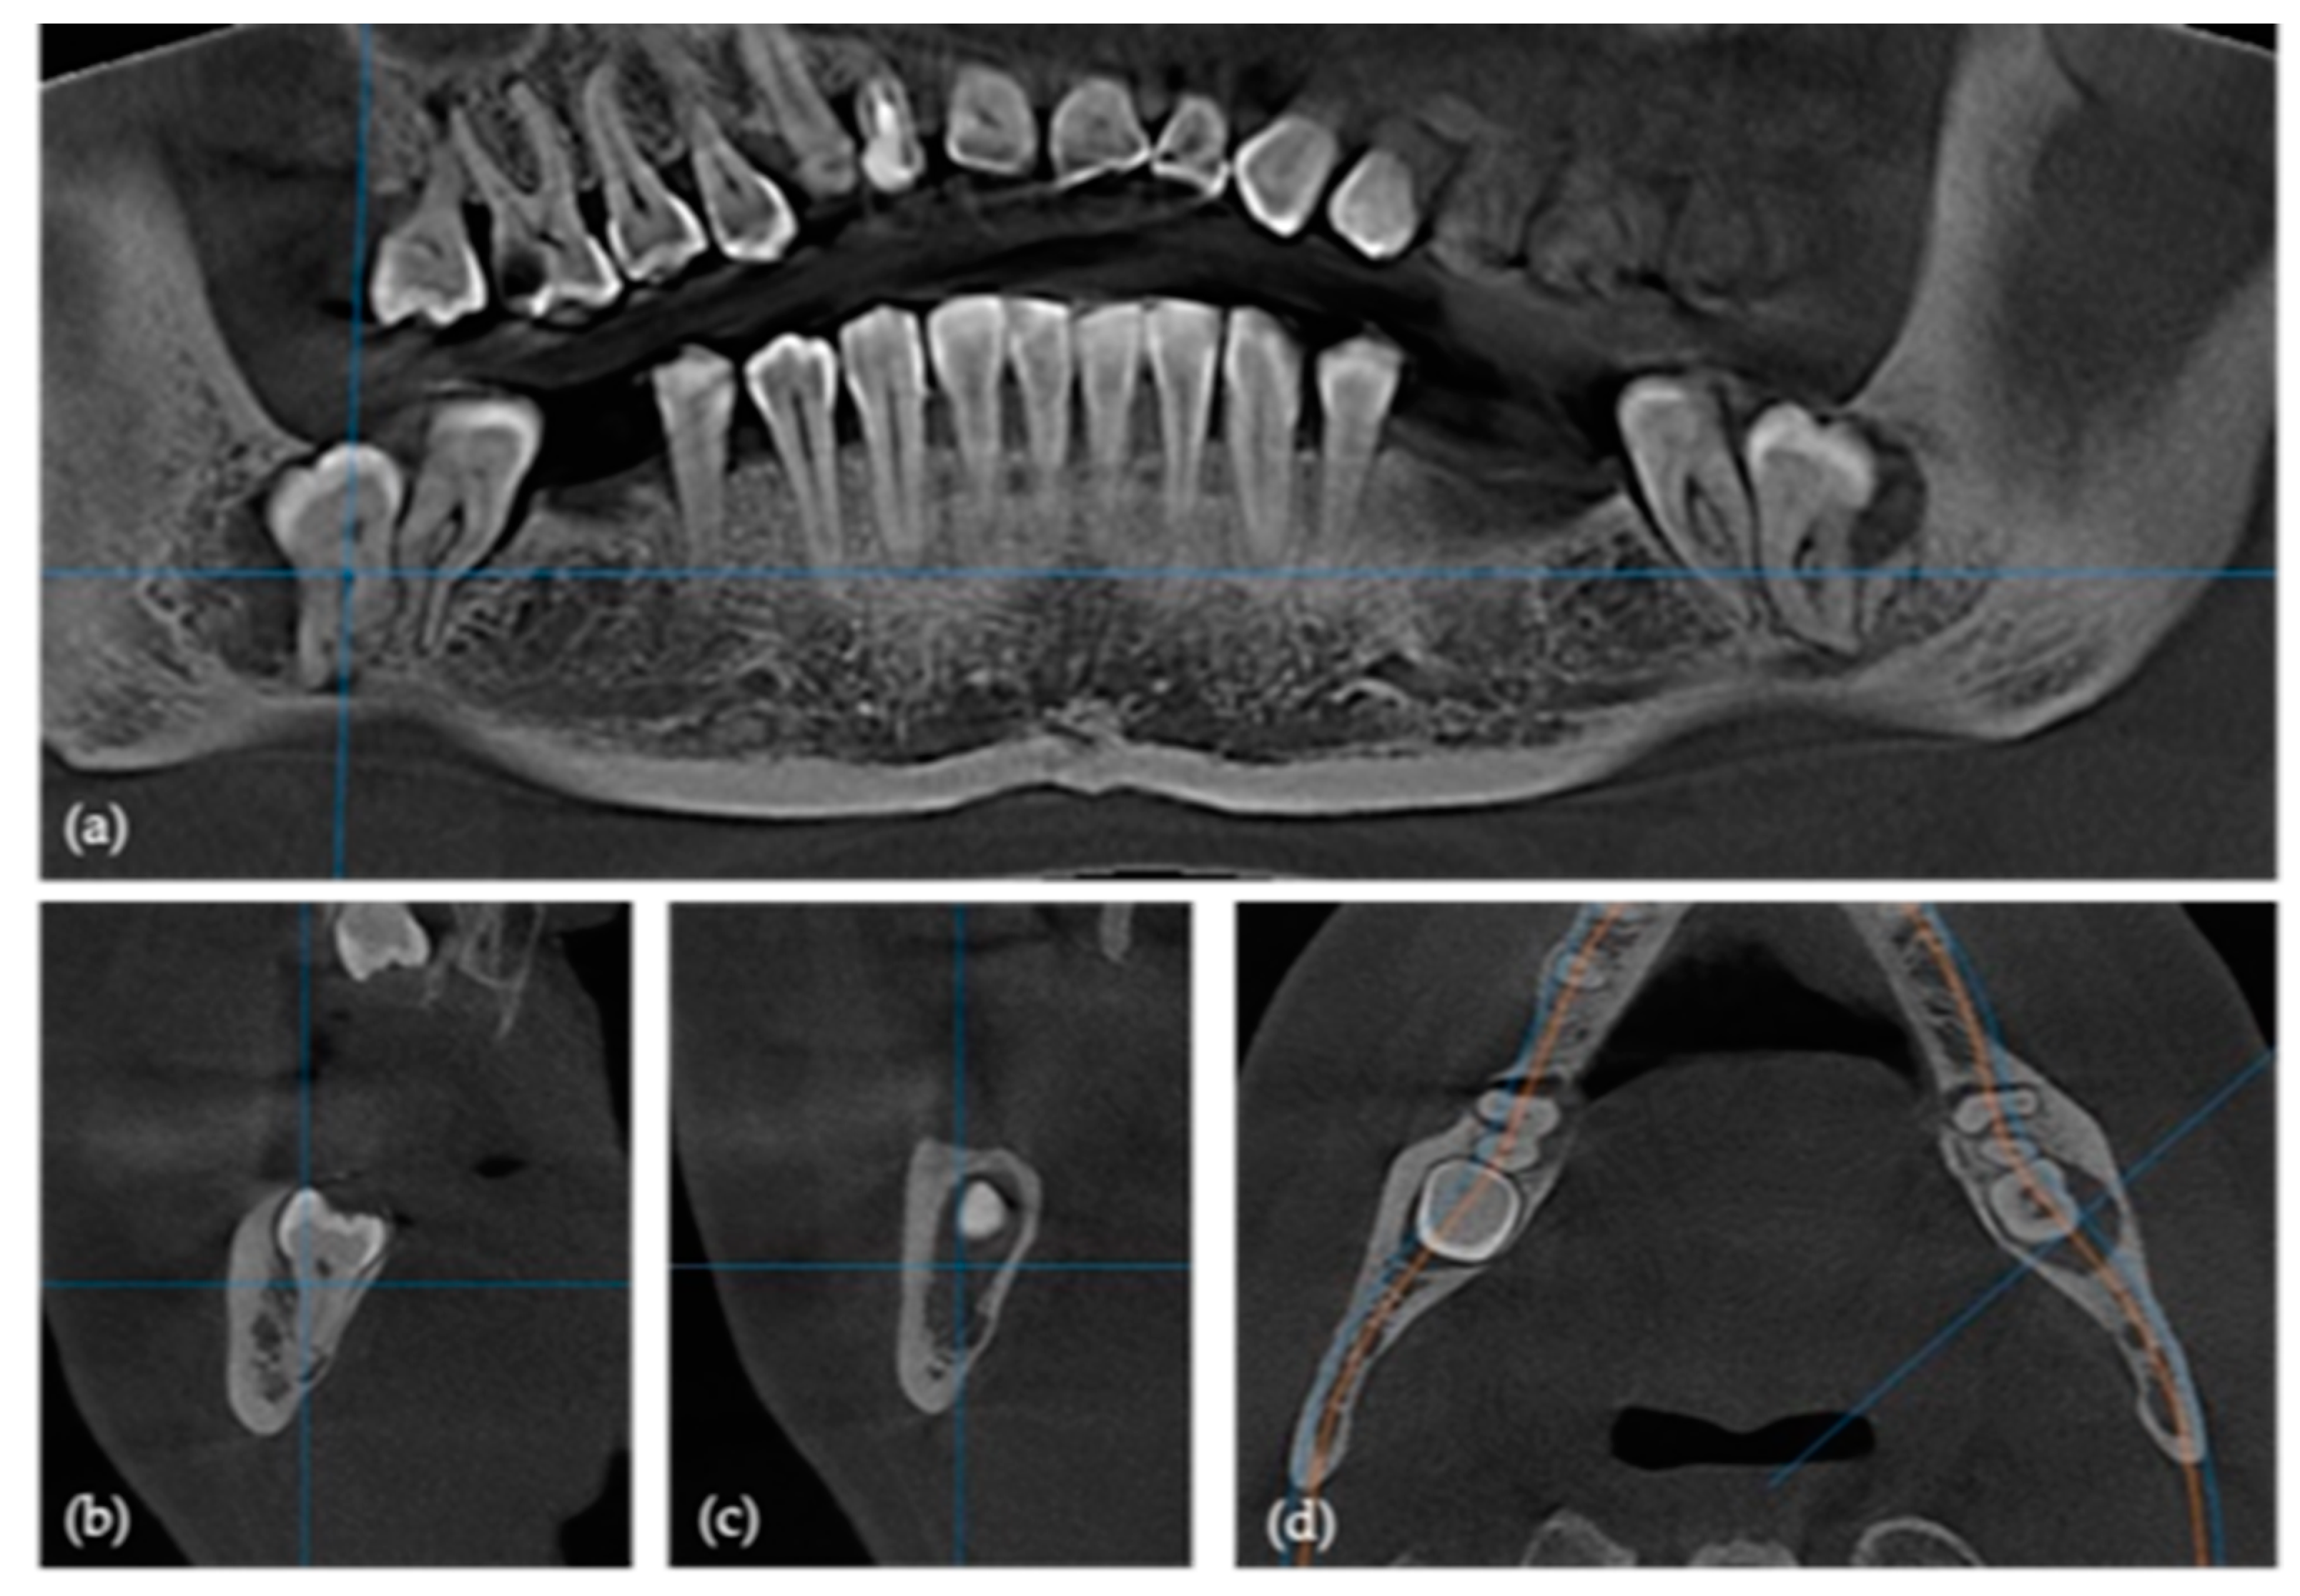

2.2. Pre-Surgical Cone Beam Computed Tomography (CBCT)